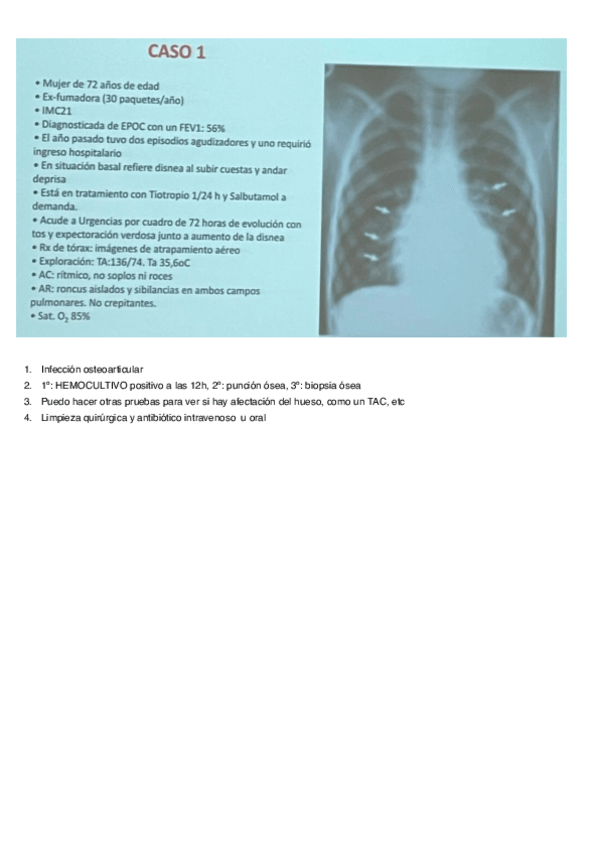

He publicado nuevos apuntes de 3º Microbiología Médica y Clínica: Casos-Clinicos-Microbiologia.pdf

4 páginas